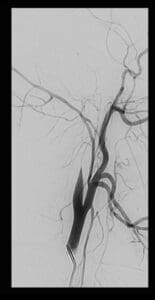

צוות מצנתרים בראשות ד"ר ולדימיר בורודצקי, מצנתר מוח בכיר ביחידה, ביצעו צנתור מוח מורכב בהרדמה מלאה שארך מעל ארבע שעות.

במהלך הצנתור המורכב התברר כי עורק התרדמה הפנימי משמאל חסום ממוצאו. החסימה הייתה עקשנית ולא ניתנת לפתיחה בדרכים המקובלות בצנתורי שבץ. לבסוף הוחלט על השתלת תומכן (סטנט) באיזור החסימה בעורק במוח, מה שאפשר הוצאת חלקי קרישי דם ופתיחת החסימה.